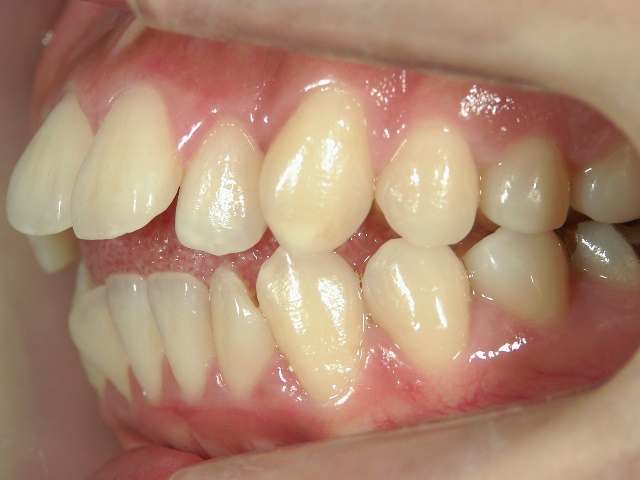

主訴:奥歯で噛んだときに前歯が噛み合わない

━━ 当院で働いている池谷彩乃さんが、前突および開咬を舌側ワイヤー矯正で治療しました。

中学生になり第二大臼歯が生えてから、真ん中の前歯2本が出てきて、八重歯も目立つようになりました。はじめは八重歯がチャームポイントだと捉えて気にしていませんでしたが、年々歯並びが悪化している気がしました。そのうち前突が原因で口が閉じづらく、寝ている時は口呼吸になってしまいました。

高校時代には、歯並びを改善しようと様々な矯正サイトを閲覧し、自分自身が開咬であることを知りました。開咬とは、上下の歯を噛み合わせた時に前歯に隙間ができることを言います。そういえば、麺を前歯で噛みきること、ハンバーガーにガブッと噛みつくことができませんでした。